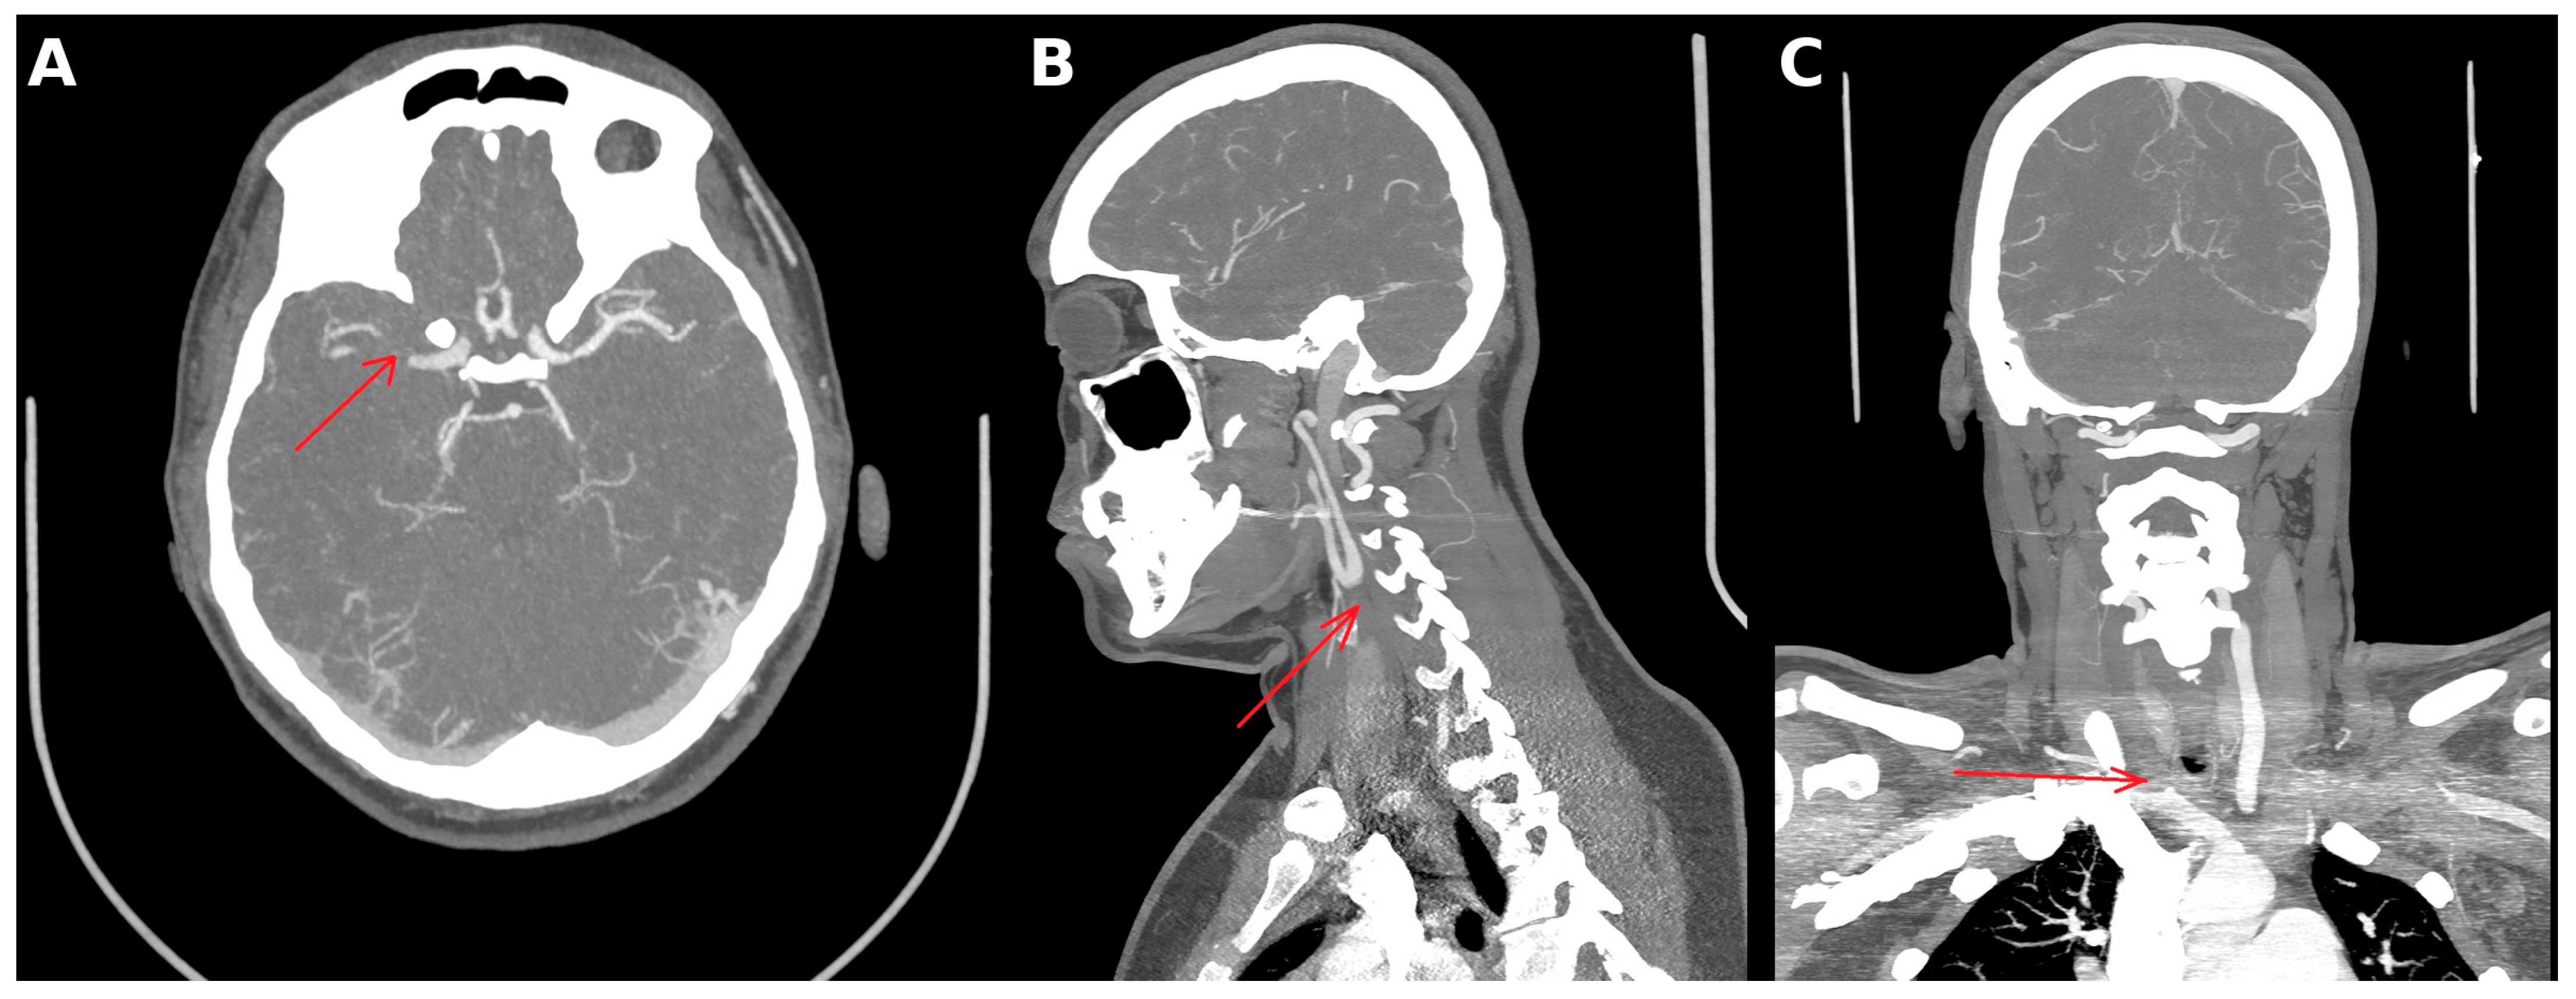

2. Case Presentation

3. Diagnostic Assessment